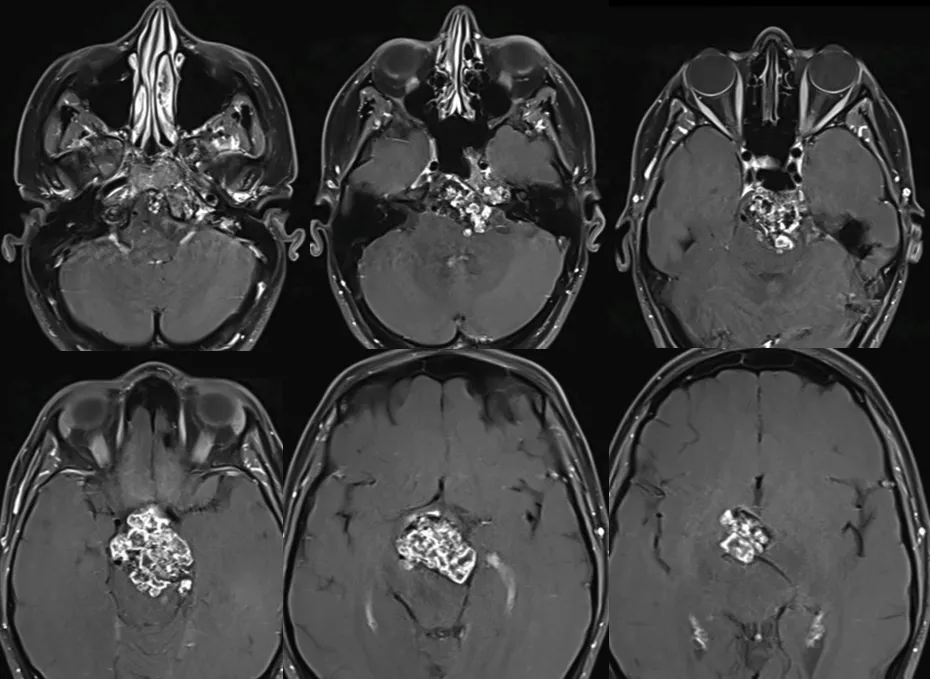

当露西因持续加重的双侧视野缺损前来就诊,检查发现颅底存在肿瘤后,术后病理也确诊为一种罕见的软骨肉瘤,且伴有钙化。下图中如同蜂窝一般密密麻麻的影像,便是露西颅底肿瘤的样子。

左侧为术后影像,右侧为术前影像,两者对比可清晰看到肿瘤的去除情况。